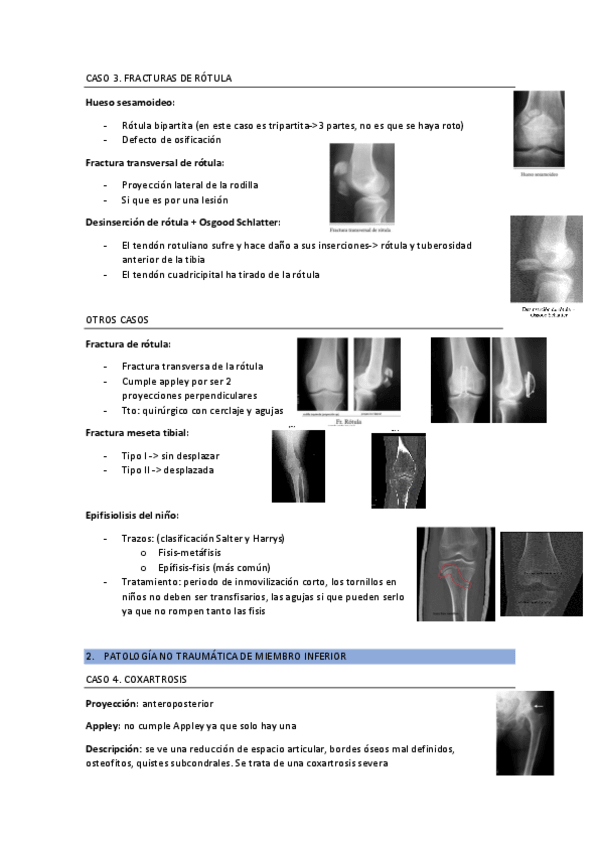

He publicado nuevos apuntes de 2º Patología y Enfoque Terapéutico del Aparato Locomotor: practica-4.-extremidad-inferiror-traumatica-pal.pdf